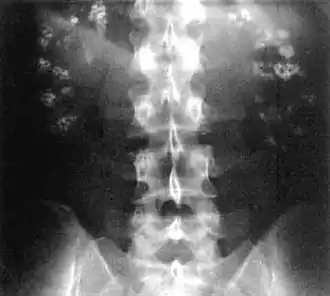

Bilateral nephrocalcinosis seen on an abdominal x-ray

Nephrocalcinosis, once known as Albright's calcinosis after Fuller Albright, is a term originally used to describe the deposition of poorly soluble calcium salts in the renal parenchyma due to hyperparathyroidism. The term nephrocalcinosis is used to describe the deposition of both calcium oxalate and calcium phosphate.[1] It may cause acute kidney injury. It is now more commonly used to describe diffuse, fine, renal parenchymal calcification in radiology.[2] It is caused by multiple different conditions and is determined by progressive kidney dysfunction. These outlines eventually come together to form a dense mass.[3] During its early stages, nephrocalcinosis is visible on x-ray, and appears as a fine granular mottling over the renal outlines. It is most commonly seen as an incidental finding with medullary sponge kidney on an abdominal x-ray. It may be severe enough to cause (as well as be caused by) renal tubular acidosis or even end stage kidney disease, due to disruption of the kidney tissue by the deposited calcium salts.